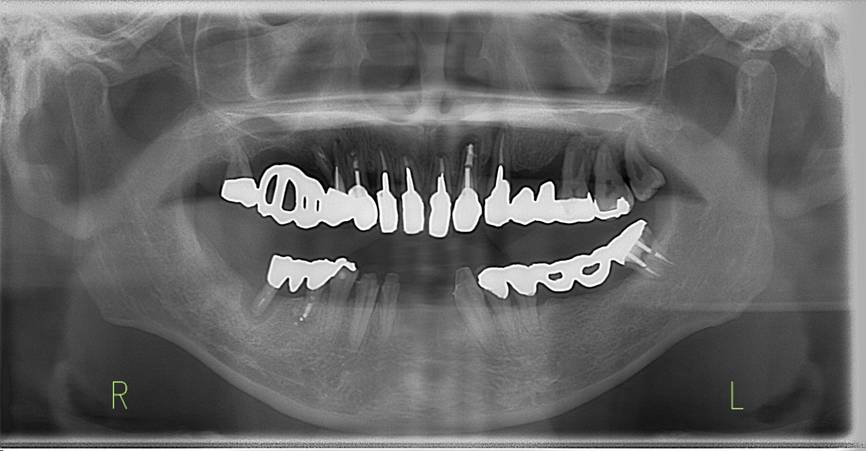

術前パノラマレントゲン写真。根の周りが黒くなり、骨がなくなっていることがわかります

治療後。歯周病で失われた骨が回復しています。使用インプラントはスプラインツイストです。

インプラント装着後6年。順調に経過しています。12か月毎のメインテナンスをしています。

術前のパノラマレントゲン写真。仮歯を支えている4本の歯は根が残っているだけで抜歯の必要がありました。

63歳術後のパノラマレントゲン。インプラントはスプラインツイスト

1990年初診時パノラマ 61歳女性

治療終了時1990

歯の破折2016年 87

201727年後。27年間に右上4、左上46、右下4の根の治療をされていた臼歯が4本歯根破折し、インプラントに置き換わっています。この間3本のインプラントには変化がありません。根の治療をした歯が破折しやすいこととインプラントが長持ちすることがわかります。

上顎 88歳。右上インプラントは25年経過、左上インプラントは2年経過しています。

下顎。右下4のジルコニア冠はインプラントです。上のレントゲン写真のあとインプラントを埋入しました。ジルコニア冠の色が改善しています。